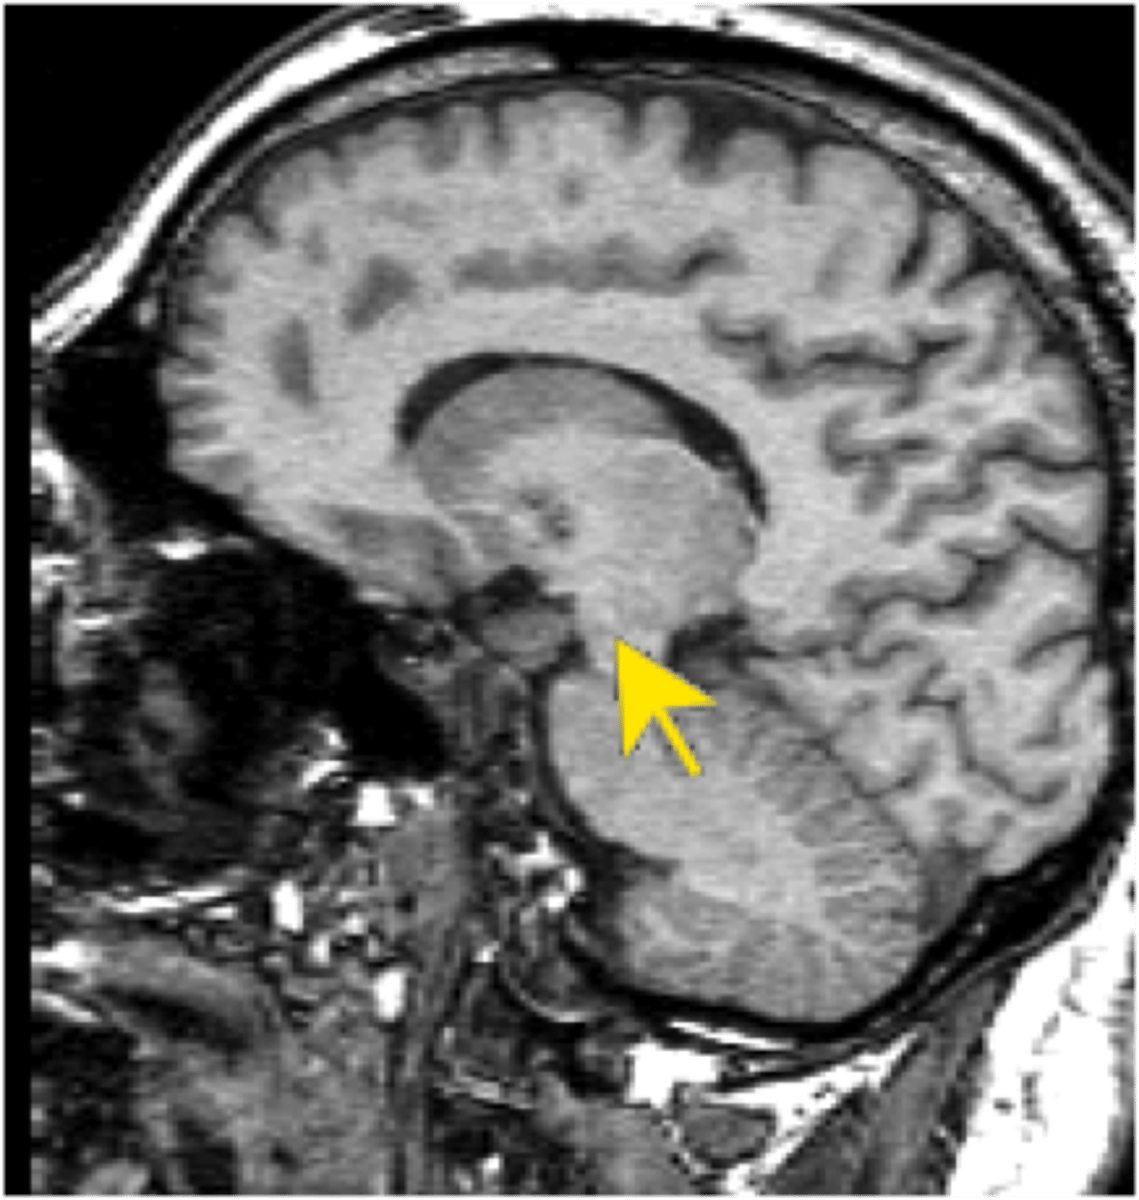

Hippocampus

A neural center located in the limbic system that helps process declarative memories for storage.

<p>A neural center located in the limbic system that helps process declarative memories for storage.</p>